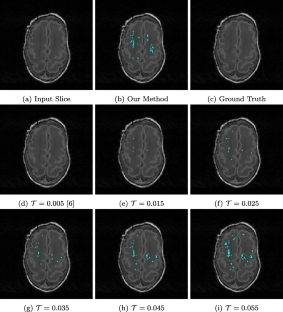

White matter injury (WMI) is the most prevalent brain injury in the preterm neonate leading to developmental deficits. However, detecting WMI in magnetic resonance (MR) images of preterm neonate brains using traditional WM segmentation-based methods is difficult mainly due to lack of reliable preterm neonate brain atlases to guide segmentation. Hence, we propose a segmentation-free, fast, unsupervised, atlas-free WMI detection method. We detect the ventricles as blobs using a fast linear maximally stable extremal regions algorithm. A reference contour equidistant from the blobs and the brain-background boundary is used to identify tissue adjacent to the blobs. Assuming normal distribution of the gray-value intensity of this tissue, the outlier intensities in the entire brain region are identified as potential WMI candidates. Thereafter, false positives are discriminated using appropriate heuristics. Experiments using an expert-annotated dataset show that the proposed method runs 20 times faster than our earlier work which relied on time-consuming segmentation of the WM region, without compromising WMI detection accuracy.

Fig. 1